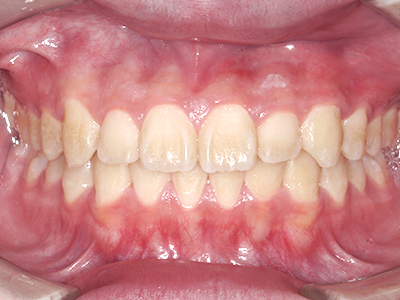

ないき歯科クリニックでは、これからあごが成長していくお子様や、歯並びが気になる成人の方など、さまざまな年代の方に対して矯正治療を行っています。

歯並びやかみ合わせを正しく整えると、笑顔や発音の自信につながり、むし歯・歯周病・口臭の予防にも役立ちます。

ないき歯科クリニックでは、上あごの成長不足を補い、鼻呼吸を獲得しつつ歯列を整え、将来のお口をより健康な状態にすることをゴールに定める矯正治療をおこなっています。